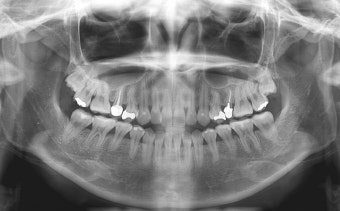

- 임플란트·틀니는 3~6개월마다 정기 검진 필수. 초기 3개월은 적응 기간.

- 임플란트 보철물로 인한 저작 소리나 불편함은 교합 조정으로 해결 가능.

- 합병증(나사 풀림, 파절 등)은 초기 자각 어려움 → 정기 검진 필수.

- 조기 검진은 작은 문제도 빠르게 발견 → 큰 문제 예방 가능.